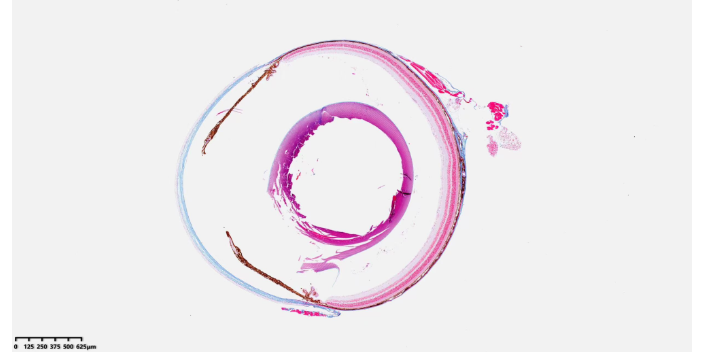

HE染色是病理實驗中**常用的染色方法。其原理基于蘇木精和伊紅兩種染料對不同細胞結(jié)構(gòu)的親和力。蘇木精是堿性染料,它能將細胞核染成藍紫色。這是因為細胞核中的核酸帶有酸性基團,與蘇木精中的陽離子結(jié)合。在染色過程中,蘇木精染色液需要一定的時間來充分與細胞核反應(yīng),時間過短會導致細胞核染色不充分。伊紅是酸性染料,對細胞質(zhì)等細胞成分有親和力,能將細胞質(zhì)、細胞外基質(zhì)等染成粉紅色。伊紅染色后,細胞的整體結(jié)構(gòu)更加清晰。染色完成后,切片需要經(jīng)過脫水、透明和封片等步驟。通過HE染色,病理學家可以在顯微鏡下清晰地觀察到細胞的形態(tài)、大小、排列方式以及組織的結(jié)構(gòu)層次。例如在**病理診斷中,HE染色能夠初步判斷**的類型、分化程度等。正常組織與病變組織在HE染色下會呈現(xiàn)出明顯的差異,如炎癥組織中的細胞浸潤、**組織中的異型性細胞等都能被直觀地發(fā)現(xiàn)。病理切片染色質(zhì)量控制,確保結(jié)果一致性。浙江實驗服務(wù)

病理圖像分析是病理實驗中的重要環(huán)節(jié),它借助計算機技術(shù)對病理切片圖像進行定量和定性的分析。首先要獲取高質(zhì)量的病理切片圖像,可以通過掃描儀或顯微鏡配備的圖像采集系統(tǒng)。采集到的圖像需要進行預(yù)處理,如調(diào)整亮度、對比度等,以使圖像更清晰,便于分析。在定性分析方面,病理圖像分析軟件可以識別不同的組織區(qū)域和細胞類型。例如在**病理圖像中,可以區(qū)分腫瘤細胞和正常細胞,識別腫瘤細胞的異型性特征,如細胞核的大小、形狀、核仁的大小等。在定量分析方面,軟件可以測量細胞的大小、密度、細胞間距離等參數(shù)。對于免疫組織化學染色后的圖像,還可以對染色強度進行量化分析。例如在研究**的增殖情況時,可以通過測量Ki-67陽性細胞的比例來定量評估腫瘤細胞的增殖活***理圖像分析為病理研究和診斷提供了更加客觀、準確的數(shù)據(jù)支持,減少了人工分析的主觀性。病理實驗方案設(shè)計咨詢,滿足個性化需求。上海分子實驗

病理切片數(shù)字化掃描,便于數(shù)據(jù)存儲與分析。浙江實驗服務(wù)